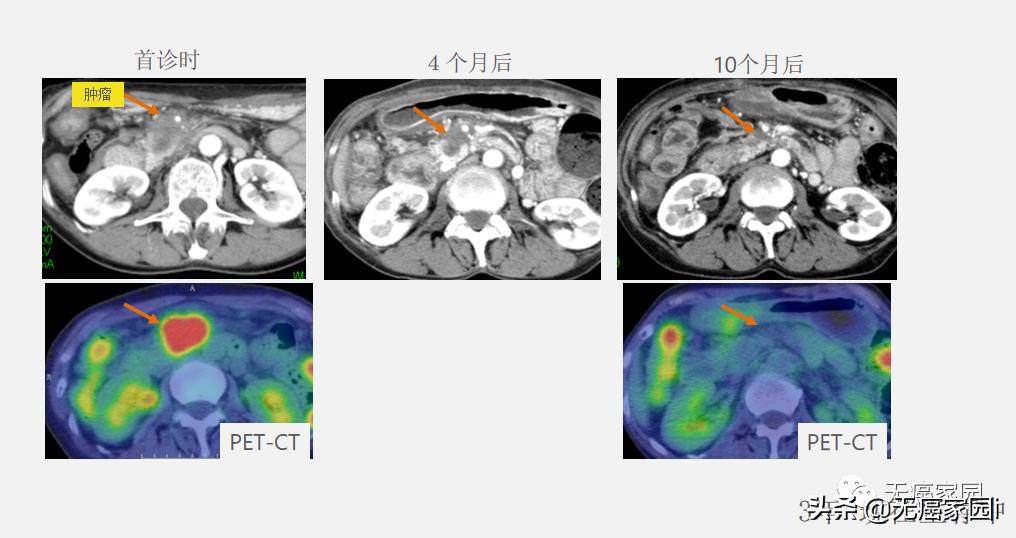

局部浸润胰头癌的病例示意图:无法手术的胰头癌患者通常寿命是不到一年的,而图中病例目前已存活3年。

对术后局部复发病灶的质子线治疗,也有长期生存的希望。如图所示, 粒子线治疗后的中位生存期为26.1个月,明显长于其他治疗方法。